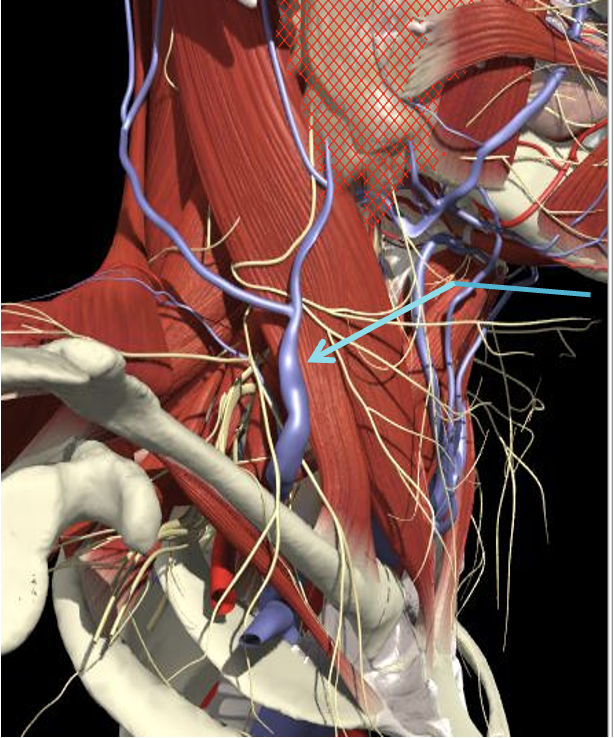

Structures to Avoid

Nerves in Posterior Triangle

Accessory nerve

Lies on LS, enters 1cm cranial to EP posterior border of SCM and runs on line to between middle and lower third of trapezius.

Should inject splenius and levator over 1cm above EP

Cervical plexus cutaneous branches

Mid point of posterior border

Inject levator above this point

Landmarks

Cervical plexus

Midpoint of SCM (EP)

Middle and lower third of Trapezius